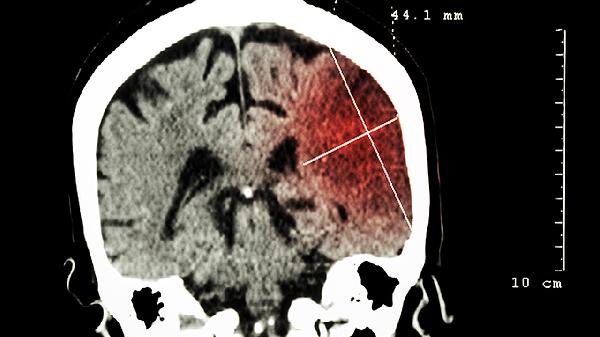

无脑儿主要表现为颅骨穹窿缺如、大脑半球完全或部分缺失,通常合并脊髓脊膜膨出等神经管畸形。 1、颅骨缺失 颅顶骨及...